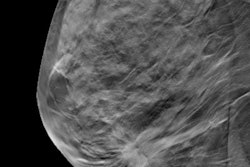

Thanks to the power of digital breast tomosynthesis (DBT), it may be possible to use observation to follow radial scars on breast images rather than surgically excise them, according to research presented Wednesday at the annual meeting of the American Roentgen Ray Society (ARRS) in Honolulu.

A team led by Dr. Ingolf Karst of Northwestern University in Chicago discovered that observation with DBT was a viable alternative to biopsy after switching to the technology from digital mammography. Karst and colleagues found that no radial scars discovered on core biopsy and followed with DBT were upgraded to invasive cancer or ductal carcinoma in situ (DCIS) on excision.

So the researchers investigated whether the use of DBT -- thus the better visualization of findings such as architectural distortion -- would increase the detection and upgrade rates of radial scars, compared with digital mammography, and what factors might contribute to choosing surveillance over surgery.